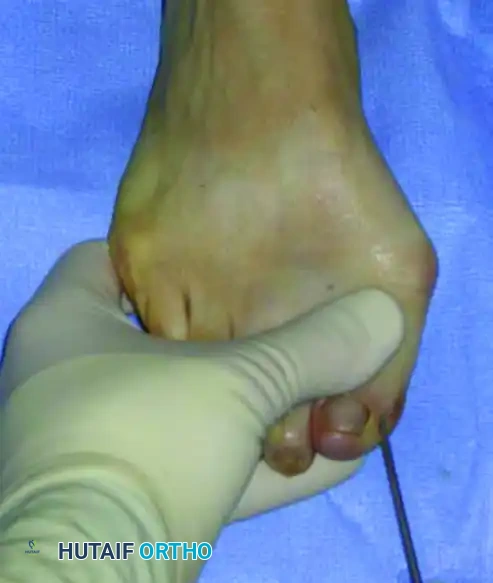

يتم وضع المريض على ظهره على طاولة العمليات. يستخدم الجراح دعامة خاصة تحت الركبة للسماح بثني الركبة بزاوية تسعين درجة، مما يضع القدم في وضعية مستوية وثابتة على الطاولة لتسهيل العمل الجراحي.

يتم وضع جهاز الأشعة السينية المباشرة بجانب المريض، بينما يقف الجراح الرئيسي أمام المريض مباشرة عند نهاية الطاولة. هذا الترتيب يتيح للجراح رؤية محورية واضحة للقدم وسهولة في استخدام جهاز الأشعة للتأكد من كل خطوة.